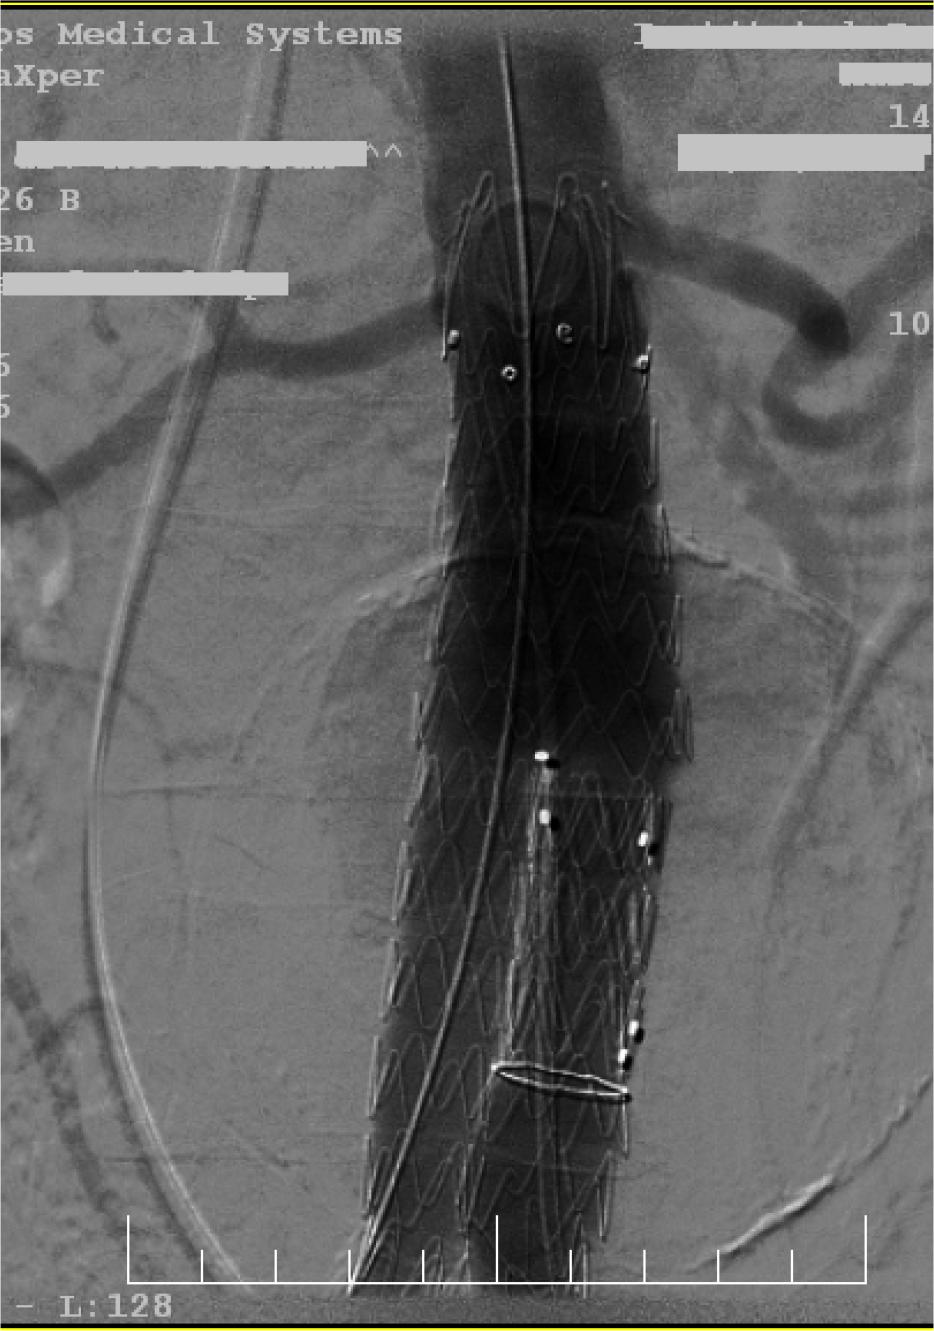

Using the same vascular access site, an Endurant II 25-13166 mm endo-prosthesis was carefully deployed just distal to the right renal artery, extending through the right common iliac artery down to the iliac bifurcation. The device was precisely positioned to ensure an adequate proximal and distal sealing zone, considering the length and diameter of the infrarenal neck and iliac vessels. From the contralateral femoral access, a 14-French Sentrant Medtronic sheath was introduced, through which an additional contralateral extension with an Endurant II 16-13-124 mm endoprosthesis was advanced and deployed, covering the terminal abdominal aorta and extending into the left common iliac artery. The use of a large-bore sheath facilitated smooth delivery and deployment of the devices. Post-deployment balloon angioplasty was performed to optimize endoprosthesis apposition and expansion, reducing the risk of endoleaks and ensuring secure fixation. Completion angiography demonstrated correct positioning with full expansion of the stent graft components, achieving complete exclusion of the aneurysmal sac. A minimal type II endoleak was observed, originating from lumbar artery collaterals, which was hemodynamically insignificant and expected to resolve spontaneously.

Fluoroscopy: deployment of the aortic endograft.